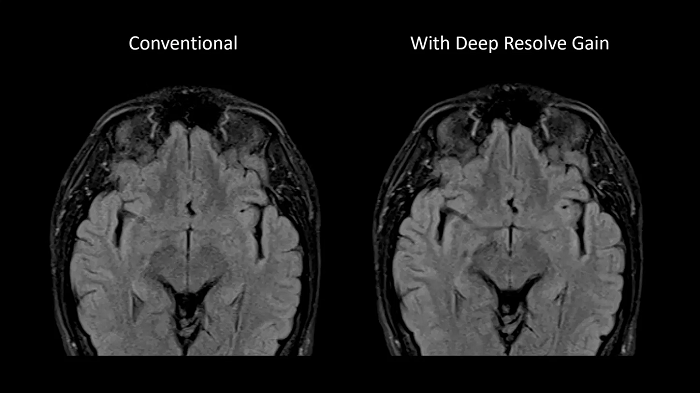

Deep Resolve Gain

Deep Resolve Gain, a constructive technique, utilizes individual quantitative noise maps in the reconstruction process for targeted denoising. It increases image quality to ensure the best diagnostic abilities and is available for a wide range of sequences.

80 cm bore MAGNETOM Free.Max

Image Courtesy: University Hospital Erlangen, Germany | Image-ID: 4aaaa0297